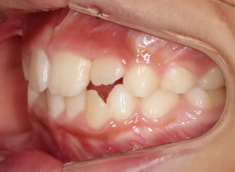

小児期ケース:叢生(ガタガタ)

治療法:拡大プレート+フルパッシブブラケット(クリアスナップ)

治療前